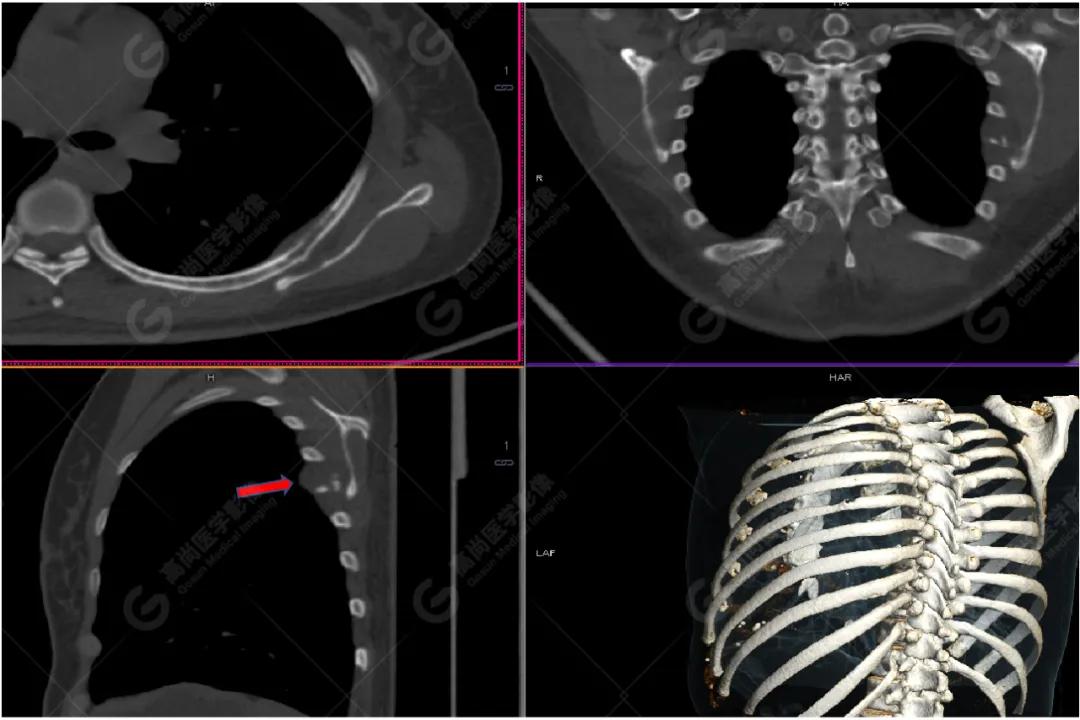

PET/CT

影像图

左胸一后肋溶骨性骨质破坏,周围伴软组织形成,FDG代谢增高,SUVmax为10.9。

找到引起骨痛病灶,病因:原发?转移?感染?

宫颈一片状稍低密度影,FDG结节样代谢增高,SUVmax为10.2。

最终诊断: 宫颈癌伴肋骨单发骨转移。